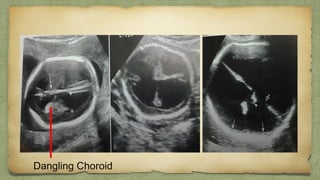

Dangling Choroid

๏ฑ May be Unilateral orMay be Unilateral or

Bilateral.Bilateral.

๏ฑ Usually transient & benign.Usually transient & benign.

๏ฑ Seen in fetus normallySeen in fetus normally

between 16 โ€“ 21 weeks, afterbetween 16 โ€“ 21 weeks, after

which they start regressingwhich they start regressing..